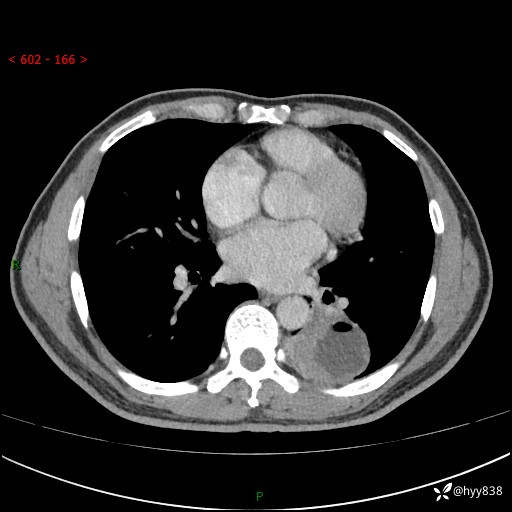

胸部CT平扫

增强